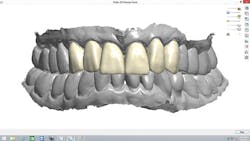

A 67-year-old female executive presented after becoming very self-conscious about the appearance of her anterior teeth (figure 1). During the consultation appointment, a thorough examination was performed, and scanned intraoral 3-D images and impressions (Trios, 3Shape) were obtained. Both arches and the bite registration were scanned (figure 2).

The scans were immediately evaluated chairside with the patient. When the maxillary scan was viewed from the occlusal aspect (figure 3), the extent of the rotation of her two lateral incisors became dramatically apparent to the patient. It was also pointed out and explained to her that both central incisors were positioned lingually due to the severe crowding of her arch.

Figure 2: Intraoral 3-D images and impressions of both arches and the bite registration were obtained and used to help plan and explain the treatment to the patient.

Figure 3: The extent of the rotation of the lateral incisors became dramatically apparent when viewing the maxillary scan from the occlusal aspect.